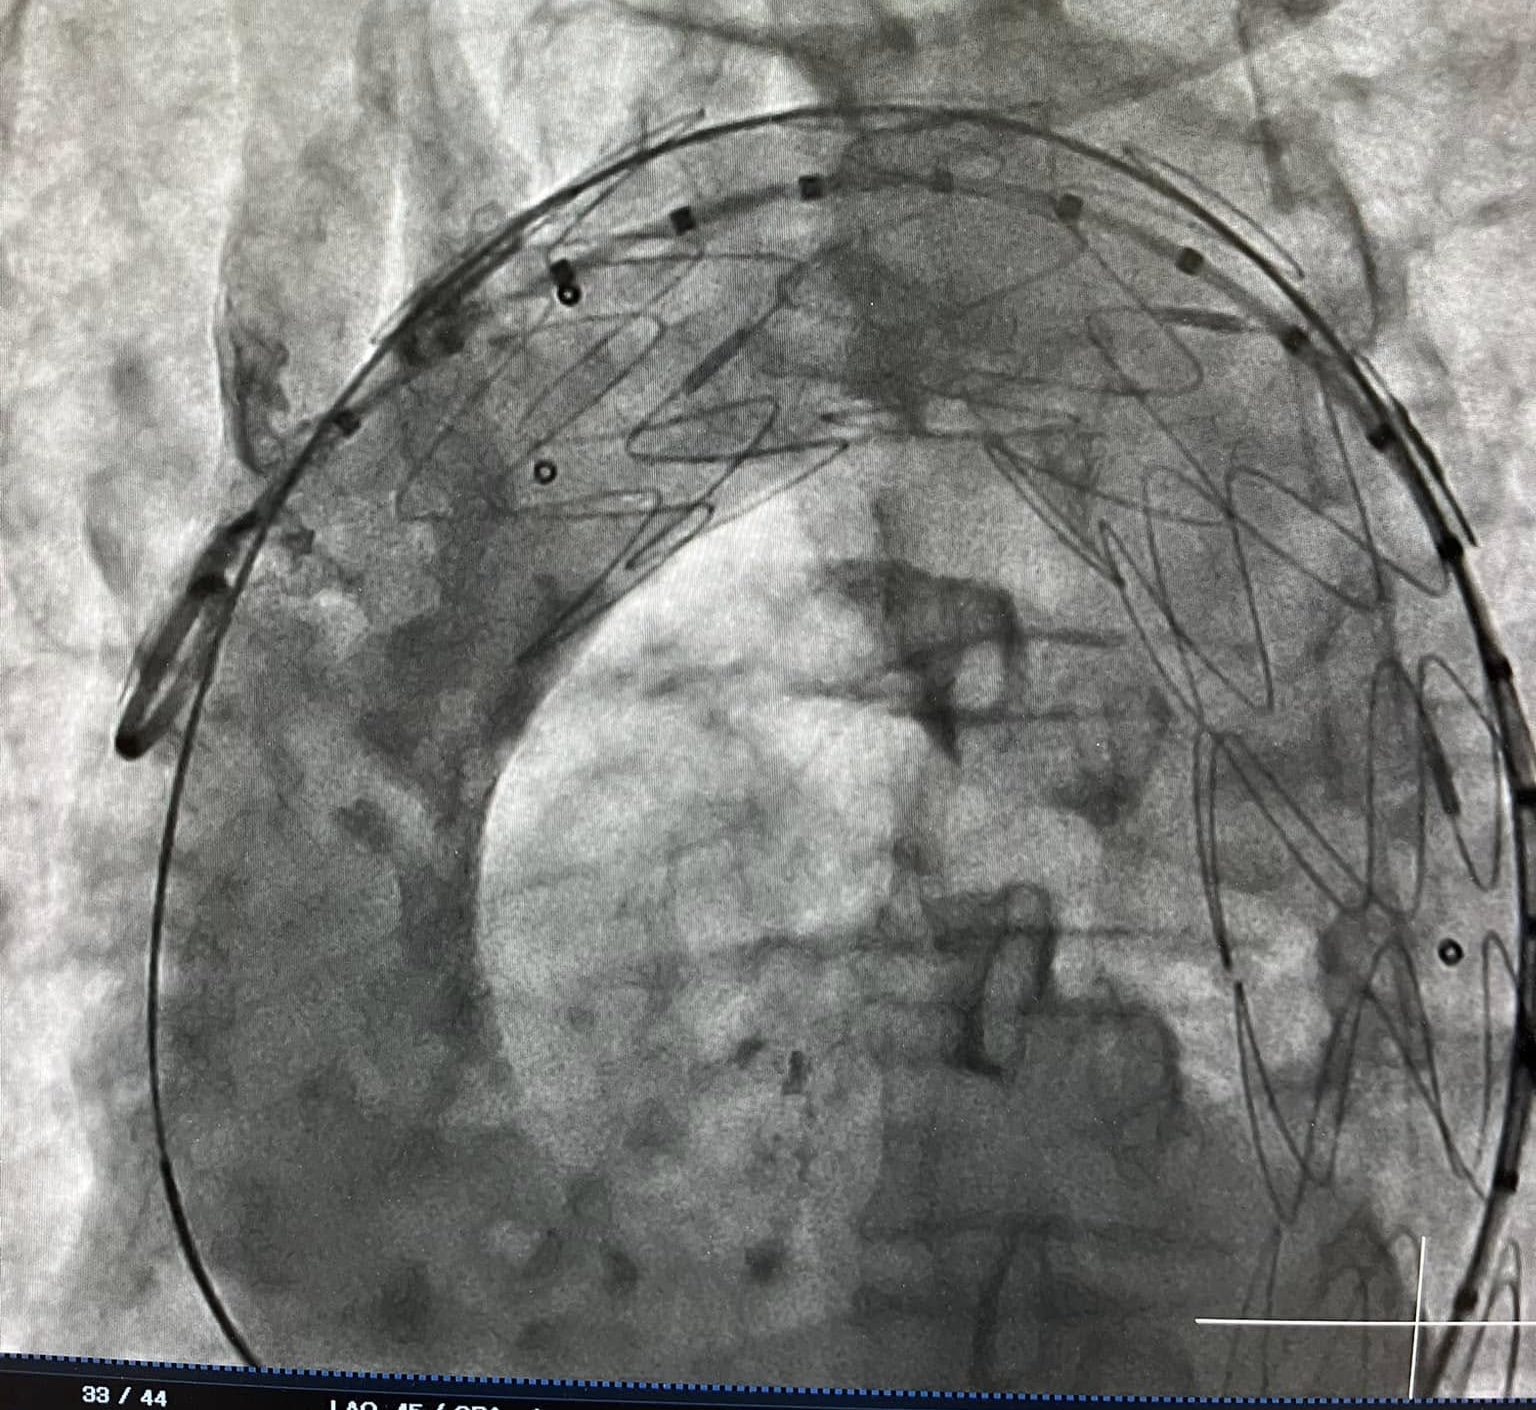

Hình ảnh can thiệp của bệnh N.V.K trên máy chụp DSA

Sau khi hội chẩn, các bác sĩ đã lựa chọn phương án điều trị tốt nhất cho bệnh nhân can thiệp đặt stent graft động mạch chủ ngực. Gia đình bệnh nhân và bệnh nhân đã tin tưởng quyết định can thiệp tại BVĐK tỉnh Thanh Hoá.

Ngay sau can thiệp, bệnh nhân N.V.K hết tình trạng đau ngực trái và được xuất viện trong tình trạng khoẻ mạnh sau 3 ngày can thiệp.